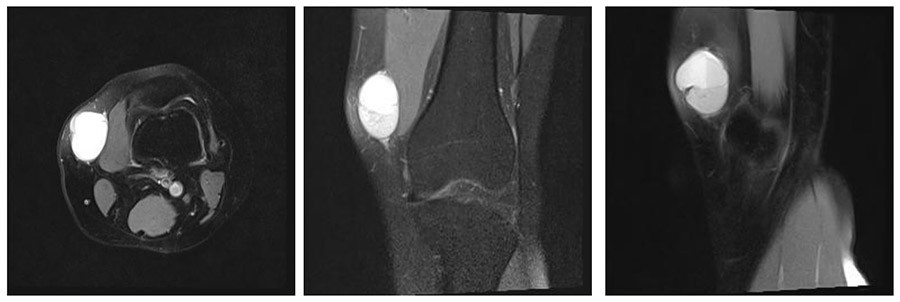

İlk Başvuru: MR’da diz medialde düzensiz sınırlı heterojen yumuşak doku kitlesi görülmekte